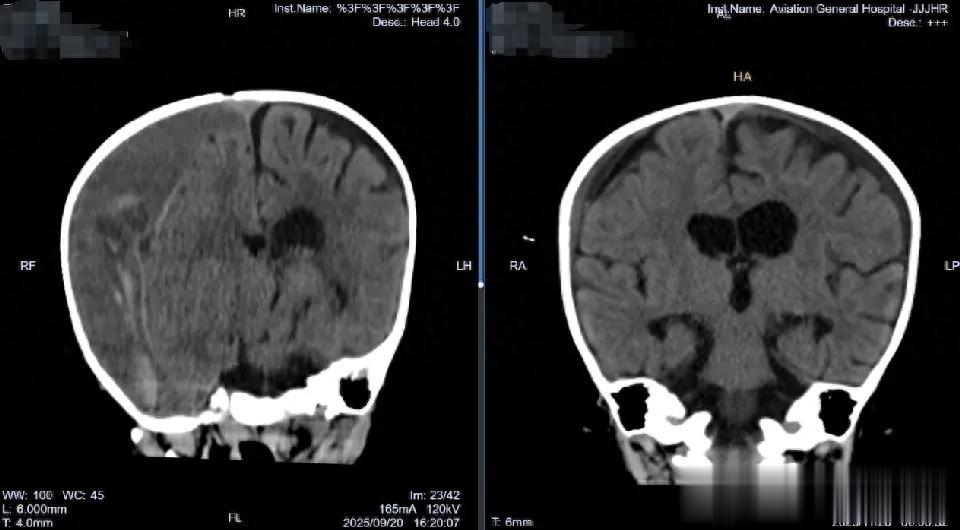

通过放置在腹壁外的引流管,医疗团队每天监测引流情况,并逐步调整引流瓶高度,促进大脑自然复位。这一外引流设计避免了在感染风险期植入永久性分流装置。经过近两个月的恢复,2025年11月底,瑶瑶再次接受手术,移除了硬膜下-腹腔分流管。次日复查头颅CT显示:双侧硬膜下仅残留少量低密度影,脑组织复位良好,中线结构居中。